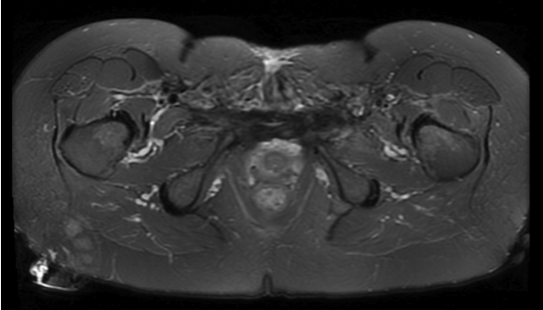

Postoperatively, the patient had an uncomplicated, self-resolving ileus and otherwise unremarkable hospital course. She was discharged after 4 days of hospitalization. The final pathology report confirmed the diagnosis of a solid ABC with negative margins. She was most recently seen in clinic 14 months postoperatively with no recurrence of symptoms or of the mass as indicated by repeat contrast MRI (Figure 3).

Figure 3. Axial T2-weighted MRI taken 14 months postoperatively showing no evidence of recurrent or residual tumor.